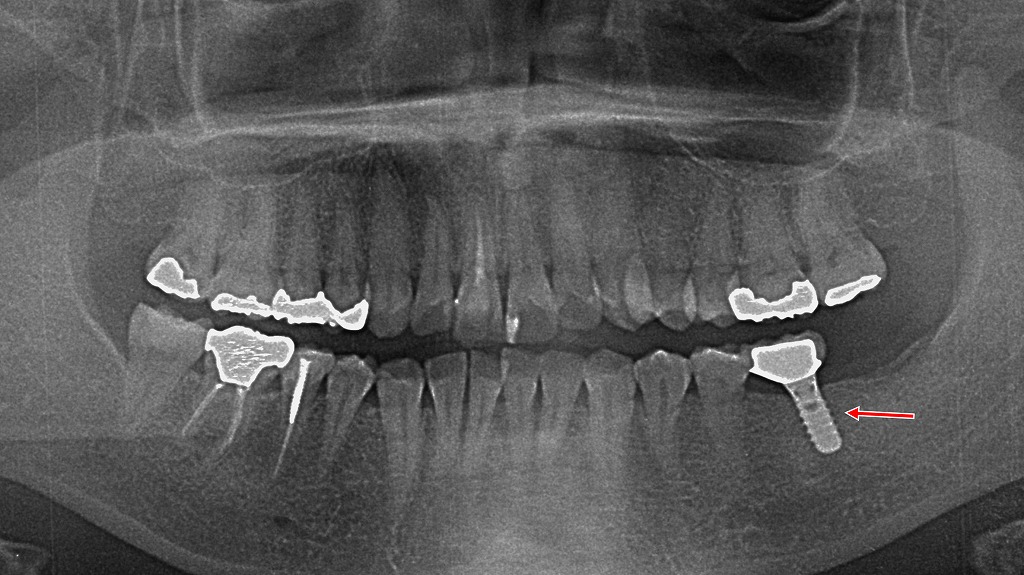

インプラント治療により機能回復

レントゲン画像の矢印部は、抜歯後にインプラント治療を行い、失った歯の機能と噛み合わせを回復した例です。

インプラントは、周囲の歯を削らずに単独で補える治療法で、見た目だけでなく「しっかり噛める」状態を長期的に維持できる選択肢の一つです。